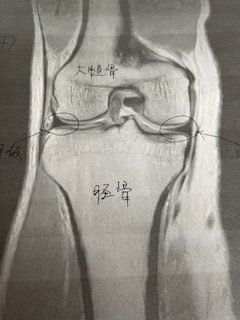

今回のテーマは「膝」 待ってました! 一番興味がある部位ですね

ふん ふん なるほど こうやって捉えるのね(また一つ描写方法が見つかりましたね)

今回のテーマは「膝」 待ってました! 一番興味がある部位ですね

ふん ふん なるほど こうやって捉えるのね(また一つ描写方法が見つかりましたね)